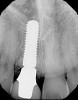

Fig 7. Preoperative radiograph showing previous endodontic therapy on tooth No. 8.

Figure 7

Plugging into digital workflows provides opportunities to integrate CAD/CAM technologies at every step of the treatment process for dental implants. In another example, a patient presented with a failing tooth No. 8 (Figure 6 and Figure 7). After discussing treatment options, the patient chose to forgo any treatment to address tooth and soft-tissue asymmetries and wanted to proceed with a dental implant-supported restoration without additional treatment. After integrated 3-dimensional planning, the tooth was extracted, and then an implant and the final custom CAD/CAM abutment (titanium base with zirconia supra-structure) were placed with a provisional restoration in the same visit (Figure 8 and Figure 9). Soft-tissue grafting was also done at the same visit to address the deficient buccal tissue height on No. 8 (Figure 10). At 3 months, the patient presented for the final restoration, with excellent healing around the implant (Figure 11) and soft-tissue healing guided by the custom abutment (Figure 12).